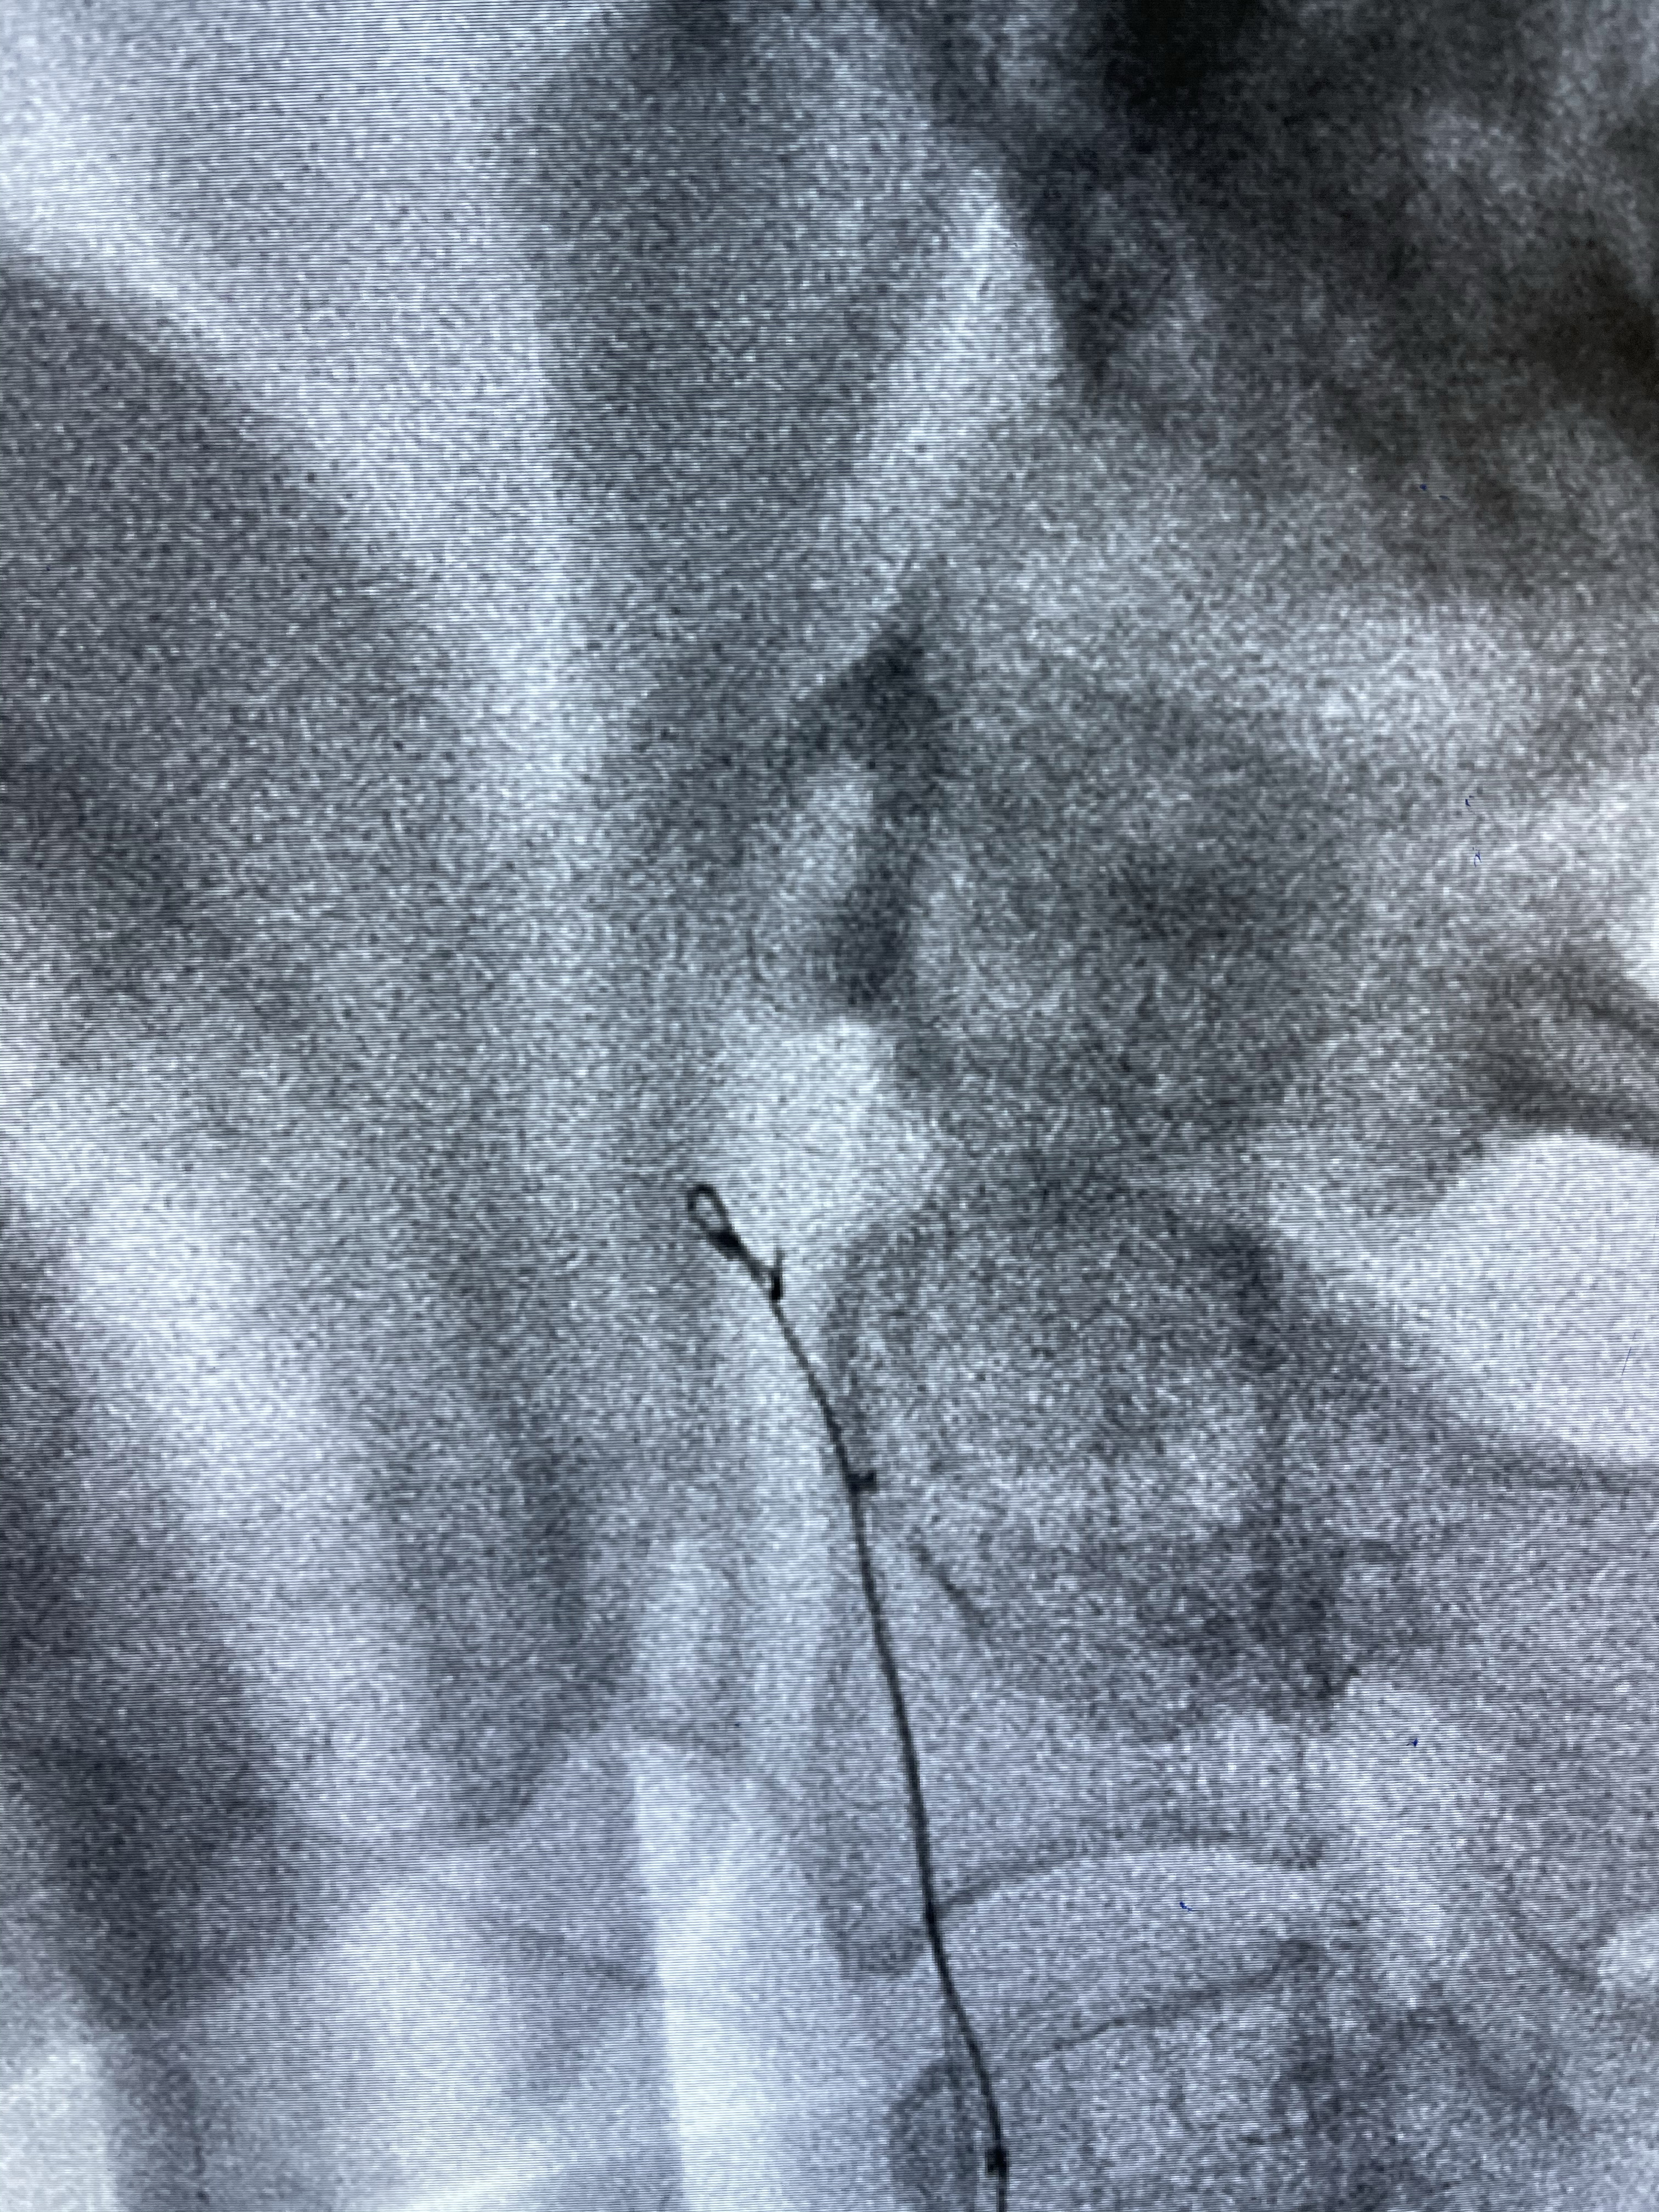

DA导引导管到位

工作角度造影

Eterprise4.0-23mm支架导管到位

Echelon10 45°角微导管塑形后到位

8mm-40cm微弹簧圈成篮